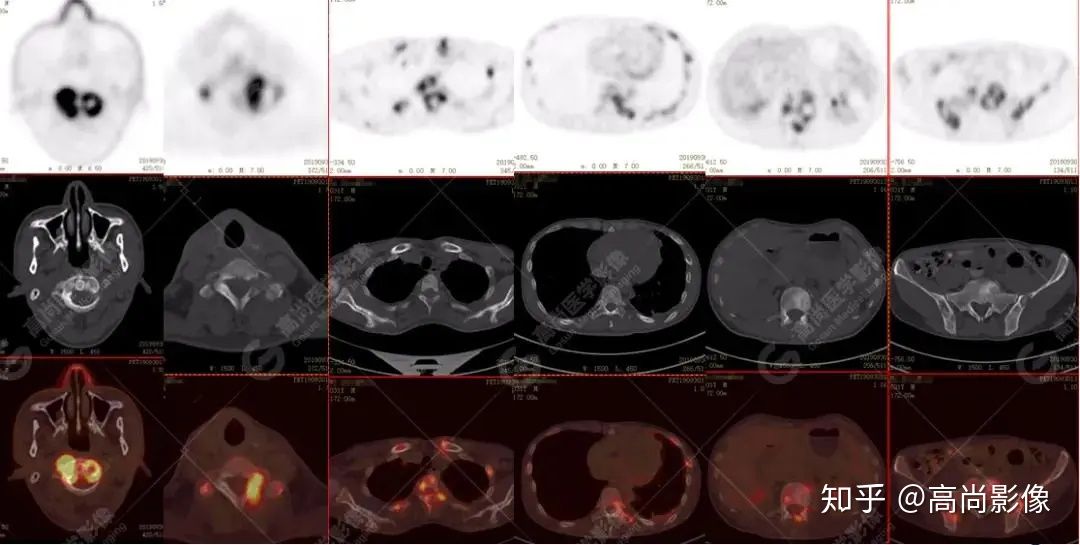

脊柱多發(fā)椎體及附件骨質(zhì)破壞,代謝不均性增高

全身多處骨質(zhì)破壞,代謝不均性增高

全身多發(fā)高代謝腫大淋巴結(jié),中央代謝缺損

左肺上葉尖后段及下葉背段多發(fā)簇狀斑點(diǎn)狀高代謝灶

左側(cè)胸膜結(jié)節(jié)樣增厚,代謝不同程度增高

【PET/CT提示】雙肺、左側(cè)胸膜多發(fā)結(jié)節(jié)影,全身多處骨質(zhì)破壞,全身多發(fā)淋巴結(jié)腫大,代謝攝取不均勻性增高。